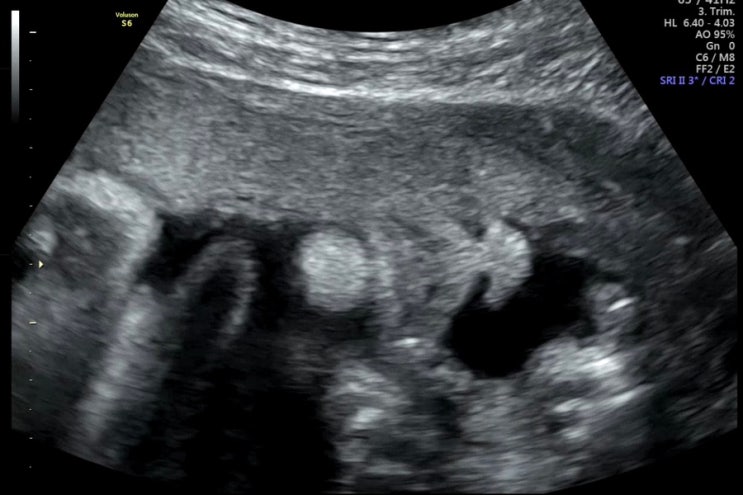

세가온산부인과 제왕절개 상세 후기

나중에 내가 보려고 쓰는 제왕 후기,,(긴글주의) 입원실 후기는 아래에 있움 ! https://m.blog.naver.com/b...